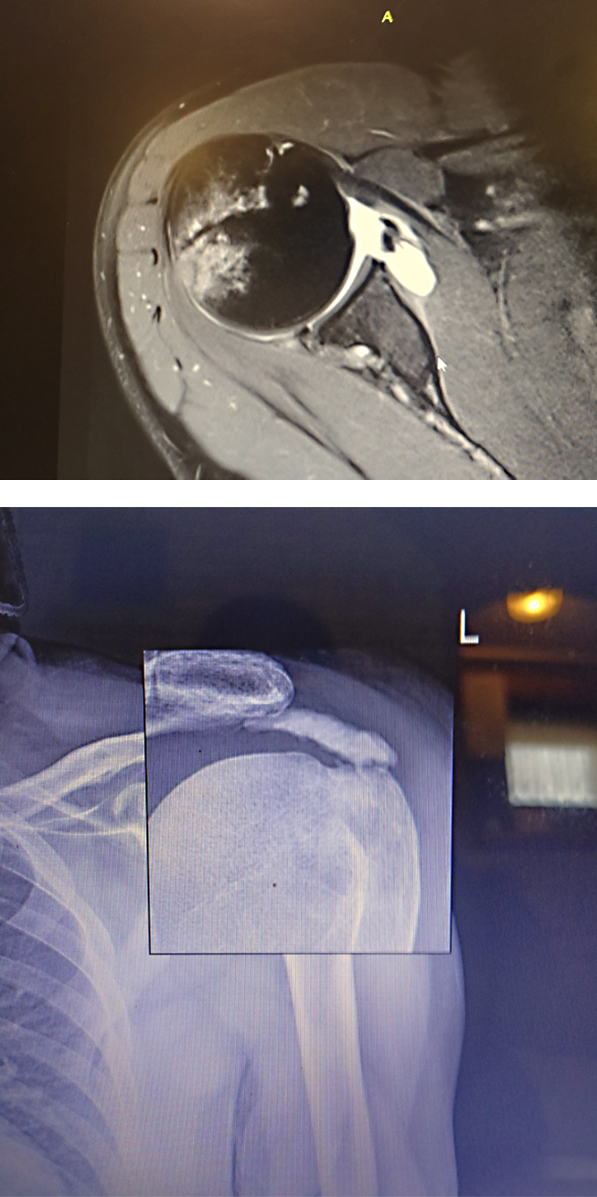

3D rekonstrukcija preloma proksimalnog dela nadlakatne kosti |

Nakon kliničkog pregleda, do postavljanja dijagnoze, sledi i dodatna, radiološka dijagnostika: rendgenski, ultrazvučni (UZ), pregled magnetnom rezonancom (Magnetic Resonance Imaging - MRI), ili kompjuterizovana tomografija (CT – skener).

Govoreći o rendgenskom snimanju, dr Medenica se osvrće i na učestalu pojavu da pacijenti samoinicijativno obavljaju MRI preglede, i sa već spremnim nalazom dolaze na pregled, pa zato naglašava da rendgenska metoda ne treba da se zaobilazi ili da se “preskače”. Pregled magnetnom rezonancom je izvanredna metoda za dijagnostiku muskuloskeletalnog sistema, ali je ona tek treći korak radiološke dijagnostike.

Na rendgenu može da se vidi mnogo toga što ukazuje na mogući problem, a što se na MRI slabije, ili čak uopšte ne vidi. Primer za to je impindžment određenih kostiju ramena, humerusa (nadlakatne kosti) i akromiona (natplećke) iznad nje, što rengden nesumnjivo detektuje. Dr Medenica objašnjava da postoje tri tipa akromiona: natplećka sa površinom okrenutom prema zglobu, koja je potpuno ravna, natplećka koja je malo savijena i kukasto savijena natplećka. Ukoliko je površina akromiona ravna, glava humerusa se normalno pokreće i nema impindženta; kod malo savijene natplećke, postoji predispozicija za impindžment, a kad je kukasto savijena, impindžment izaziva velike bolove. Sve to se veoma pokazuje na rendgenskom snimku, koji veoma dobro prikazuje i kalcifikate, posebno one starije i već formirane, te u određenim slučajevima dalja radiološka dijagnostika nije potrebna.

Najviše dijagnostički važnih informacija pruža magnetna rezonanca, koja je bezbedna i bez štetnog jonizujućeg zračenja. Ona pokazuje i kost, i hrskavičavo, i druga meka tkiva, kao i krvarenja, ili postojanje tumorskih promena. Važno je, međutim, da se pregled obavlja na kvalitetnom MRI aparatu, kao i da je radiolog koji ga obavlja subspecijalista za muskuloskeletalni sistem. Dr Medenica preporučuje da se i specijalisti ortopedije uključuju u analizu MRI nalaza - upoznati su sa problemom individualnog pacijenta, već imaju određeni klinički nalaz i mogu da ukažu radiologu na šta treba posebno da obrati pažnju.

Iz foto dokumentacije dr Medenice: MRI ramena |